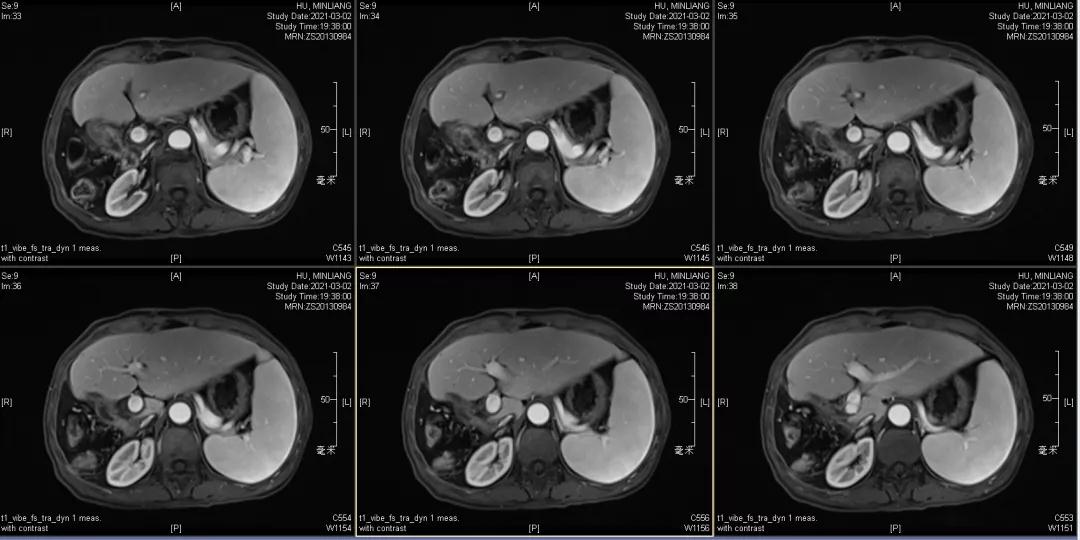

肝脏弹性超声:12kPa。腹部MRI平扫+增强:肝巨块结节性HCC(最大径18.4cm)伴肝内多发转移(最大径3.5cm),肝右静脉广泛癌栓形成;肝硬化伴门脉高压、脾大、少量腹水;肝囊肿;双肺多发转移。胸部CT平扫:两肺多发转移,两肺气肿伴肺大泡,两肺散在慢性炎症,右侧少量胸水。

Δ肝脏MRI,最大肿瘤18.4cm

肿瘤学评估(用药后2个月对比6个月):肝内主瘤明显缩小,动脉期强化降低;子灶消失;门脉右支癌栓明显缩小坏死;肺转移灶缩小,大部分消失。

Δ治疗过程中病灶影像学变化